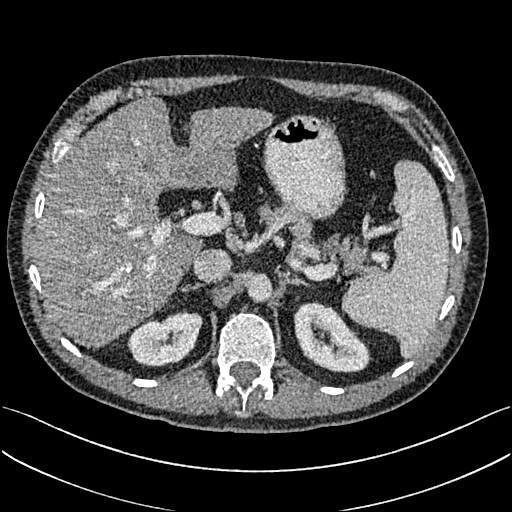

To show the denoising effect of the selected networks, we took two representative slices as shown in Figs. 5 and 7. And Figs. 6 and 8 are the zoomed regions-of-interest (ROIs) marked by the red rectangles in Figs. 5 and 7. All the networks demonstrated certain denoising capabilities. However, CNN-MSE blurred the images and introduced waxy artifacts as expected, which are easily observed in the zoomed ROIs in Figs. 6e and 8e. WGAN-MSE was able to improve the result of CNN-MSE by avoiding over-smooth but minor streak artifacts can still be observed especially compared to CNN-VGG and WGAN-VGG. Meanwhile, using WGAN or GAN alone generated stronger noise (Figs. 6g and 8g) than the other networks enhanced a few white structures in the WGAN/GAN generated images, which are originated from the low dose streak artifact in LDCT images, while on the contrary the CNN-VGG and WGAN-VGG images are visually more similar to the NDCT images. This is because the VGG loss used in CNN-VGG and WGAN-VGG is computed in a feature space that is trained previously on a very large natural image dataset [48]. By using VGG loss, we transferred the knowledge of human perception that is embedded in VGG network to CT image quality evaluation. The performance of using WGAN or GAN alone is not acceptable because it only maps the data distribution from LDCT to NDCT but does not guarantee the image content correspondence. As for the lesion detection in these two slices, all the networks enhance the lesion visibility compared to the original noisy low dose FBP images as noise is reduced by the different approaches.

As for iterative reconstruction technique, the reconstruction results depend greatly on the choices of the regularization parameters. The implemented dictionary learning reconstruction (DictRecon) result gave the most aggressive noise reduction effect compared to the network outputs as a result of strong regularization. However, it over-smoothed some fine structures. For example, in Fig. 8, the vessel pointed by the green arrow was smeared out while it is easily identifiable in NDCT as well as WGAN-VGG images. Yet, as an iterative reconstruction method, DictRecon has its advantage over post-processing method. As pointed by the red arrow in Fig 8, there is a bright spot which can be seen in DictRecon and NDCT images, but is not observable in LDCT and network processed images. Since the WGAN-VGG image is generated from LDCT image, in which this bright spot is not easily observed, it is reasonable that we do not see the bright spot in the images processed by neural networks. In other words, we do not want the network to generate structure that does not exist in the original images. In short, the proposed WGAN-VGG network is a post-processing method and information that is lost during the FBP reconstruction cannot easily be recovered, which is one limitation for all the post-processing methods. On the other hand, as an iterative reconstruction method, DictRecon algorithm generates images from raw data, which has more information than the post-processing methods.